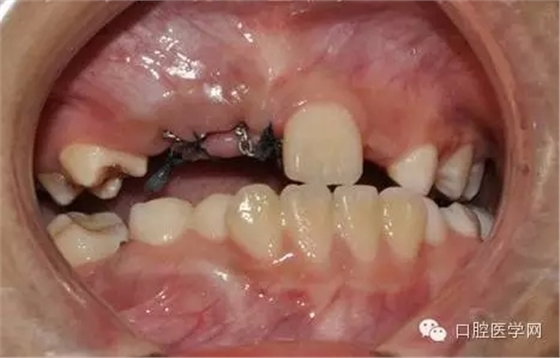

無痛麻醉(先用水果味表面麻醉,再注射。)

切開:

去除部分礙事牙囊,充分暴漏牙冠便于粘結正畸附件,并用大量腎上腺素壓迫止血。

酸蝕后

光固化型正畸粘結劑粘結鏈式牽引裝置

鏈狀正畸牽引裝置粘固后的口內情況